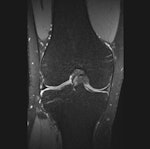

All MR knee examinations were performed with a single 3-tesla system (Trio TIM Magnetom; Siemens Healthcare) and an eight-channel phased-array knee coil with the same imaging protocol. The imaging protocol consisted of standard 2D TSE acquisitions and a SPACE 3D TSE acquisition. The 2D protocol consisted of a coronal fat-suppressed (FS) TSE intermediate-weighted (IM-w) acquisition, an axial FS TSE IM-w acquisition, and a coronal SE T1-weighted acquisition, according to the authors.

The 3D protocol consisted of a single 3D TSE acquisition in the sagittal plane with the SPACE sequence. The SPACE isotropic source data were postprocessed on a workstation (Leonardo, Siemens Healthcare) to create sagittal, coronal, and axial multiplanar reformatted (MPR) images with 1-mm slice thickness. Readers were free to use volumetric data to create MPRs in any orientation and slice thickness, they stated.

Accuracies were calculated using arthroscopy as reference standard. McNemar's test (p < 0.05) was used to compare 3D and 2D techniques. The highest diagnostic yield was obtained by the third reader (accuracies ≥ 88%). For the medial meniscus, readers performed better with the 2D technique than with 3D SPACE (accuracies 85%-88% versus 78%-80%, respectively) (p > 0.05). For the lateral meniscus and ACL, 3D and 2D techniques had similar performance (accuracies ≥ 93%). For cartilage lesions, 3D SPACE had significantly lower specificity than the 2D protocol for one reader.